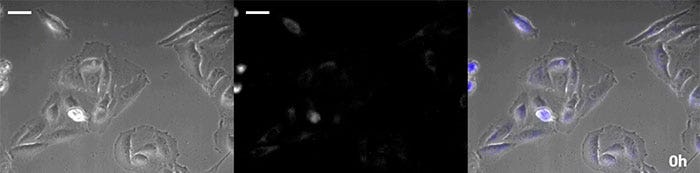

La luciferina de tipo coelenteracina posee un brillo especialmente alto; no obstante, su oxidación en la célula tras un corto período de tiempo conlleva a que sea agregada adecuadamente, lo que es esencial en las aplicaciones de observación a largo plazo. Para dar solución a este problema, se ejecutó la perfusión de células con una proteína luminiscente de alta intensidad, al mismo tiempo que un dispositivo de adición de sustrato automatizado agregó automáticamente la coelenterazina para que la luminiscencia pudiera ser monitoreada continuamente. Como resultado, se logró monitorizar la imagen luminiscente en combinación con el procesamiento de imágenes de contraste de fase durante más de 24 horas (Figura 4).

0 horas

Figura 4-1 0 horas

6 horas

Figura 4-2 6 horas